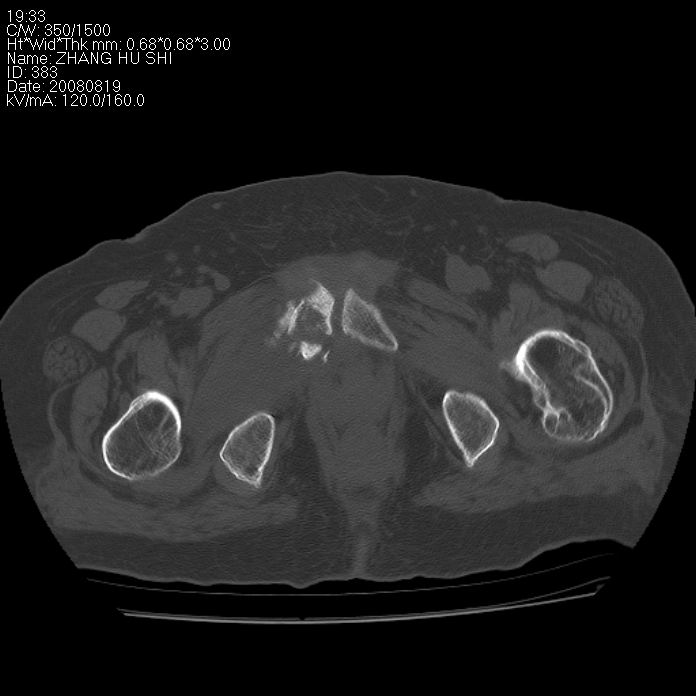

标题: CT15287:女 93岁 右髋关节疼痛 原左侧粗隆间骨折 CT发现右耻 [打印本页]

标题: CT15287:女 93岁 右髋关节疼痛 原左侧粗隆间骨折 CT发现右耻

支持转移

支持转移并周围软组织侵犯右闭孔内肌侵犯,但tb不能完全除外。

耻骨软骨肉瘤可能性大